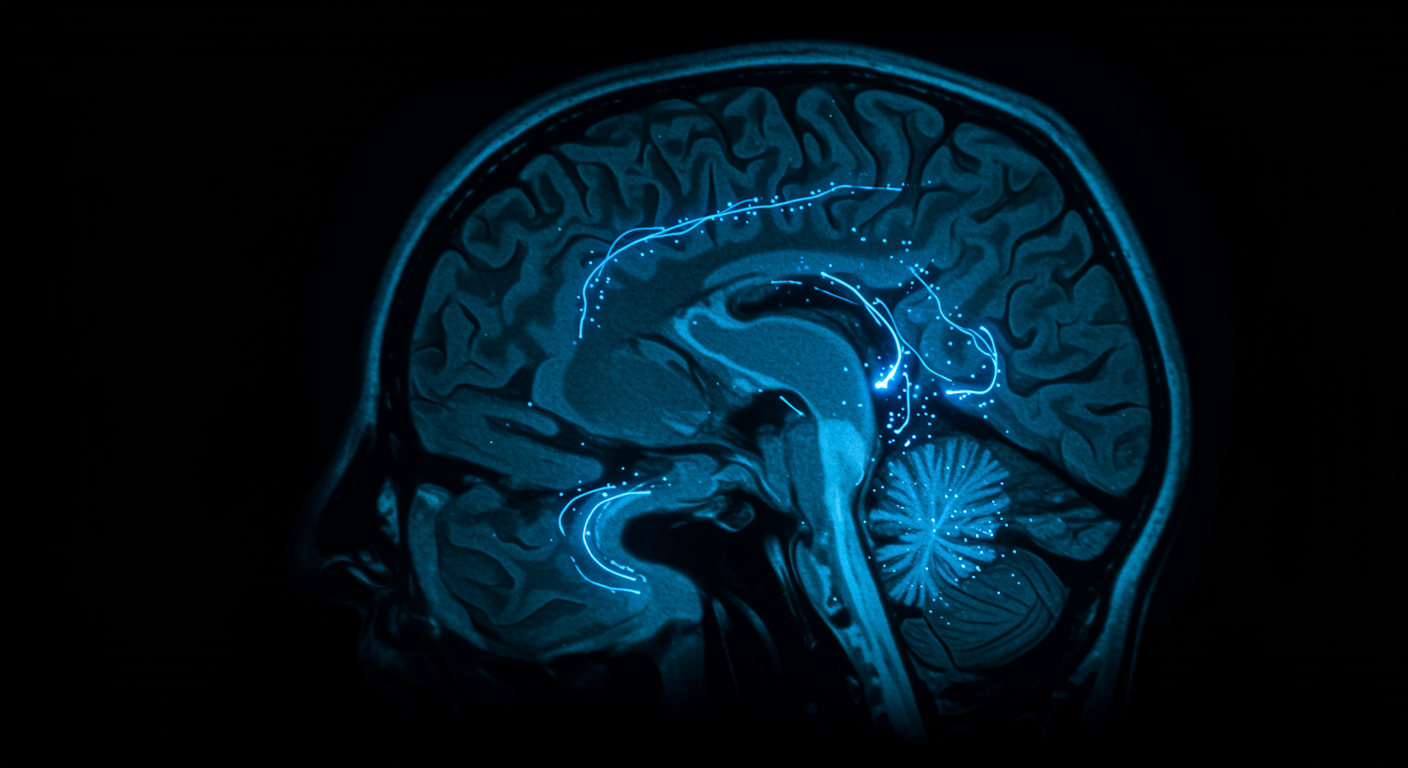

Neuroimaging studies consistently demonstrate that loneliness alters brain activity and structure across multiple networks. The “social brain” - including regions like the anterior cingulate cortex, insula, and temporoparietal junction - shows altered connectivity patterns in lonely individuals. These changes affect how the brain processes social information, regulates emotions, and responds to stress.

Loneliness activates the brain’s threat detection systems while suppressing social reward circuits. The anterior cingulate cortex becomes hyperactive to social threats, while the ventral striatum shows reduced response to social rewards. This creates a neurobiological state of hypervigilance combined with reduced motivation for social connection - a pattern that can become self-perpetuating.

Key findings from loneliness neuroscience research:

- Increased amygdala reactivity to social threats in lonely individuals

- Reduced prefrontal cortex activity during social cognition tasks

- Altered default mode network connectivity affecting self-referential thinking

- Decreased social reward network activity reducing motivation for connection

- Structural brain changes in regions involved in social processing with chronic loneliness